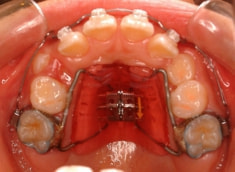

治療法:上顎拡大装置+フルパッシブブラケット(クリアスナップ)+フェイスマスク等

治療分析:日本人の反対咬合や下顎前突は、上顎の劣成長を伴なうことがほとんどで、本ケースも上顎劣成長でしたので、上顎を側方拡大と前方に牽引しました。側方拡大方法は急速拡大で正中口蓋縫合の拡大を行い、同時に横口蓋縫合を剥がす効果があり、前方牽引の効果を促進します。

治療開始後3ヶ月で、すでに前歯がジャンプしていますが、ここで注意が必要です。これは前歯の傾斜で反対咬合が一時的に解消しているだけです。ここからしっかりとフェイスマスクを使用し、上顎の牽引をしなくてはいけません。

ジャンプしただけでは「治った」ことにはなりません。今後身長と一緒に伸びてくる下顎の成長に備える必要があります。